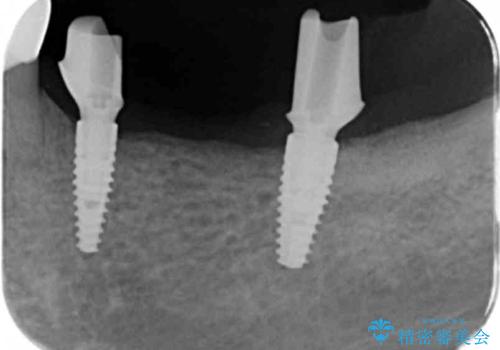

- 長年使っていた入れ歯をなくしてしまい、これを機にインプラントにしようと思い立ち来院されました。

通常長年インプラントを使用すると骨が吸収しインプラント治療が難しくなることもありますが、十分な骨が残っていたためすぐにインプラントの埋入計画を立てることができました。

- 113.3万円(インプラント×2・チタンカスタムアバットメント×2・ジルコニアクラウン×3・仮歯×3)費用は治療当時の料金となります